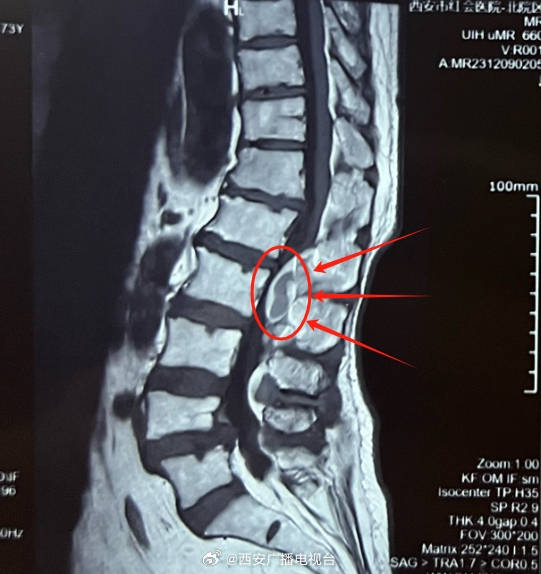

“从赵阿姨的影像资料来看,确实看到腰4-5有个轻微滑脱。”杨俊松表示“但还需要结合症状等才能给出准确诊断!”结合患者的病史、症状、体征和影像资料分析后,杨俊松认为,赵阿姨虽然影像上有腰椎滑脱但症状却与影像并不符合,没有出现坐骨神经痛症状,而是出现骨神经压迫症状——大腿前侧疼痛。症状和影像不符,结合赵阿姨长期高血压史和长期服用利血平史,高度怀疑为自发性硬膜外血肿。

脊柱病医院院长郝定均及脊柱病医院腰椎病区主任刘团江查房后指出,综合评估患者的病情,自发性硬膜外血肿可能性较高,考虑到患者病情,建议控制血压正常后尽快手术。

自发性硬膜外血肿治疗主要是血肿清除,以避免神经功能损伤加重。传统手术方式需要内固定维持腰椎生物力学稳定,但赵阿姨还有骨质疏松,钉棒固定系统容易松动。杨俊松根据赵阿姨的病情制定内镜下单侧椎板入路双侧椎管减压手术(ULBD)的方案。